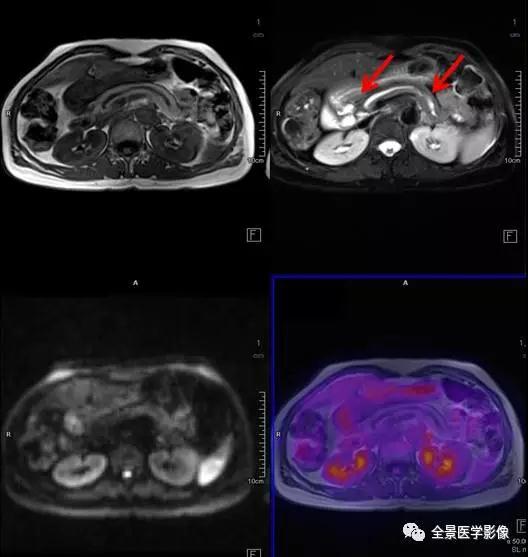

PET/MRI

肾上腺

肾上腺腺瘤

◆ 案例:中年男性,无任何症状。左侧肾上腺结合部见一长径约 1.8 cm 结节,FDG 稍摄取,考虑为肾上腺腺瘤。

点评:

根据是否有功能,可分为无功能性和功能性腺瘤。一般来说,偶然发现的肾上腺腺瘤都是无功能性的。对于无功能性腺瘤,注意定期复查。功能性腺瘤需要专科医生进行评估,最好是具备诊断肾上腺肿瘤丰富经验的放射科医师、内分泌医生和外科医生组成的评估小组。

髓样脂肪瘤

◆ 案例:中年女性,左侧肾上腺见一大小约 1.9 cm×2.1 cm 的类圆形异常信号灶,信号不均匀,内含脂肪信号,考虑为髓样脂肪瘤。

本病很少出现临床症状,多在体检时偶然发现。如肿瘤较大压迫邻近组织器官或瘤内出血坏死,可引起不适症状。但对于直径较小且无临床症状者应随访观察。